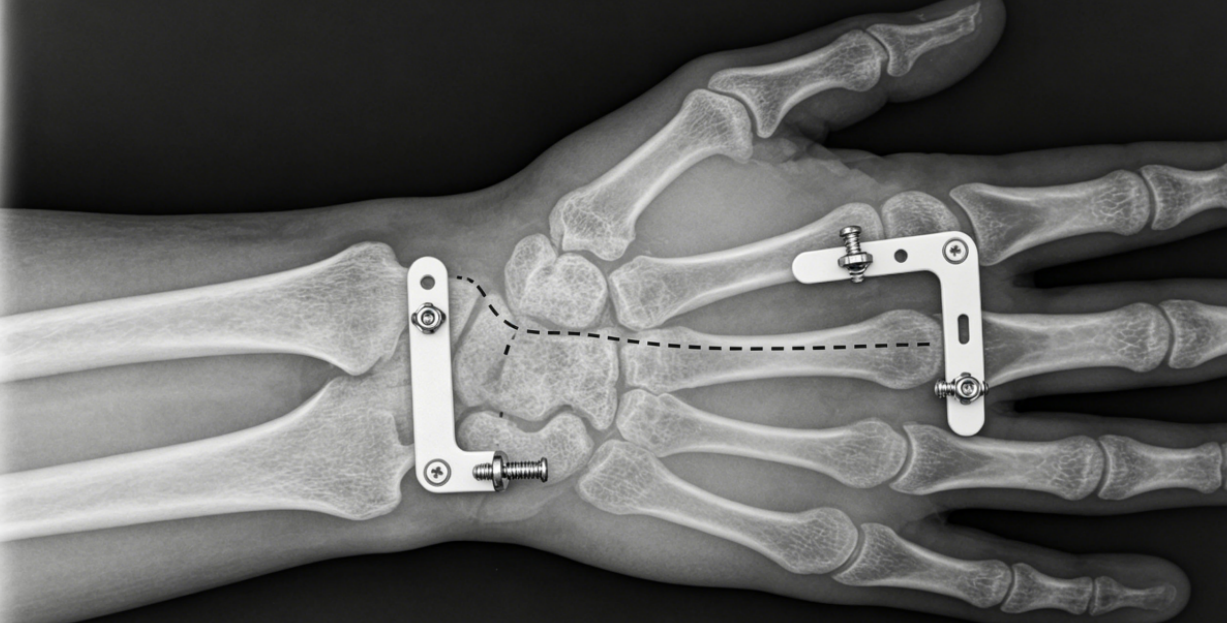

The distal radius is the most common fracture site in the upper extremity. Unstable, intra-articular, or dorsally displaced fractures require operative fixation. Volar plating has displaced dorsal plating as the standard because it avoids extensor tendon irritation and provides superior subchondral support. The volar plate is precontoured to fit the palmar concavity, and locking screws placed in the distal row create a fixed-angle construct that supports the articular surface even in osteoporotic bone.

The modified Henry approach between the flexor carpi radialis and the radial artery exposes the distal radius. The plate must be positioned proximal to the watershed line—the ridge where the volar rim meets the articular surface. Placing the plate too distally risks flexor pollicis longus rupture. Intraoperative fluoroscopy confirms screw length; screws penetrating the dorsal cortex can injure extensor tendons. Studies show that volar plating achieves 90-95% good-to-excellent functional outcomes at one year.

A 45-year-old manual laborer falls from a ladder, sustaining a AO/OTA type C2 distal radius fracture. Volar plating is performed through a flexor carpi radialis approach. The plate is placed proximal to the watershed line, and four distal locking screws capture the articular fragments. Early wrist motion begins at postoperative day three. At six months, the patient returns to heavy lifting with full range of motion and no hardware-related pain.